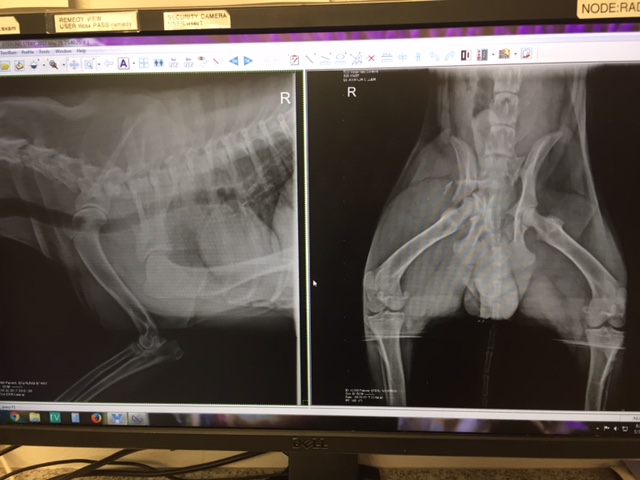

My name is 'Stirling', my pelvis was shattered when I was hit by a car in the Home Depot parking lot in Alhambra, CA on Memorial day.